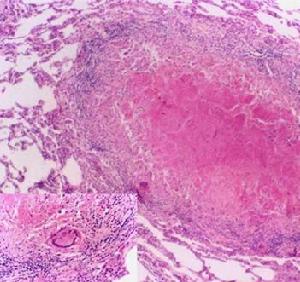

腸系膜淋巴結結核北京兒童醫院137例死於結核病患兒的屍體解剖發現30%左右有腸系膜淋巴結結核。淋巴結數目和大小不等,易融合成團塊均有乾酪樣變,有時和附近組織及器官如腸管、腹膜及大網膜相粘連。甚至結成巨大團塊似手拳樣。乾酪樣物質壞死液化可破潰至腹腔、腸腔,或通過腹壁而向外排出。病痊癒後可見散在的或廣泛的鈣化現象。

結核結節1.塗片與培養從漿膜腔液中找到抗酸桿菌是診斷結核病的重要手段,但陽性率低,僅20%~30%。此外,尚可將標本接種豚鼠做結核菌培養結核菌生長緩慢,4~6周后才出現典型病理改變。套用的Bactec460快速培養鑑定系統,採用有放射性營養物(14C棕櫚酸)為底物的7H12分枝桿菌培養基,結核菌生長期可縮短至1~3周,檢測結核桿菌需9天可鑑別結核桿菌與非結核分枝桿菌鶒藥敏試驗另需3~5天1991年套用雙相培養技術Rocheseptichek-AFB系統快速分離結核桿菌,可在2~4周出報告抗酸菌L型菌是細胞和菌落形態的一種變異,用常規方法難於培養,抗酸染色鶒不易被發現。中國套用改良的胰腖大豆蛋白瓊脂培養基(TSA-L)、快速蛋白腖瓊脂牛血清培養基、羊血培養基分離培養L型結核桿菌,1998年報導在260例復治、難治肺結核病人中培養出L型結核桿菌,陽性率29.6%。